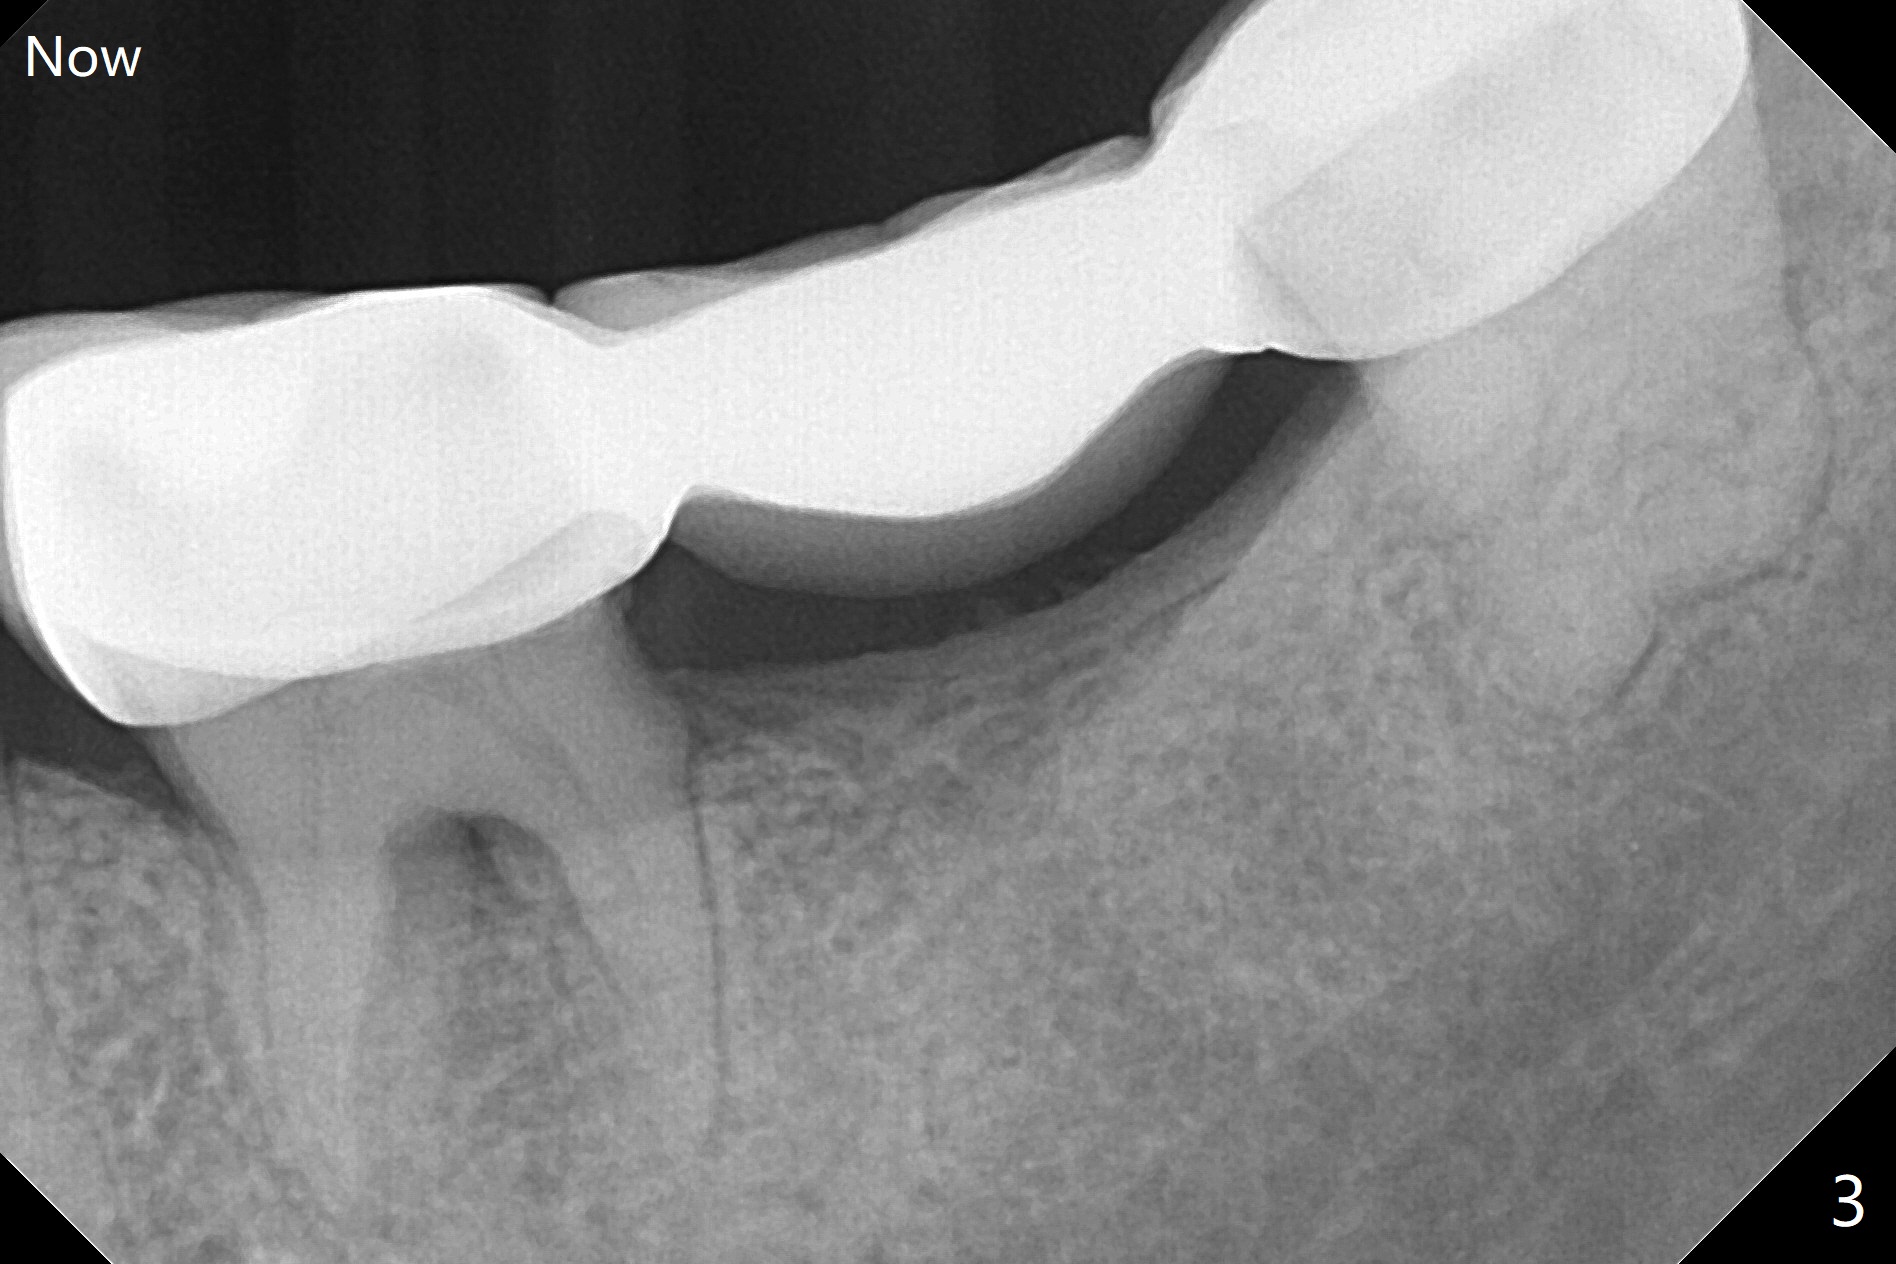

A 35-year-old woman has had guide

Return to No Caries Placement